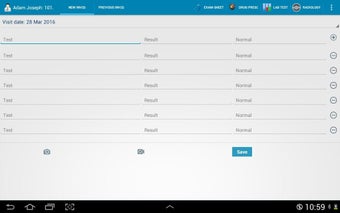

The Android Medical Records App by MedClin is a free medical records tracker app that allows users to store anamnesis, patient records, patient history, and health information. It is easy to use and provides numerous features such as username and password authentication, exporting medical data to Excel Sheet, and the ability to attach medical documents of any type. The app also has a smart search feature that allows users to search for patient information by name or ID, and even capture a photo for their profile.

In addition, the app has a blood pressure module that measures systolic, diastolic, and pulse, and allows users to export blood pressure reports to either PDF or graphs. The app also has a blood glucose (sugar) module that records blood sugar values and allows users to export blood glucose reports to either PDF or graphs. Users can also send blood pressure and blood sugar reports to their doctor. The app is compatible with multiple screens, including phones and tablets, and works on Chromebook systems. Overall, the Android Medical Records App is a great tool for patients and physicians alike for managing patient information and medical records.